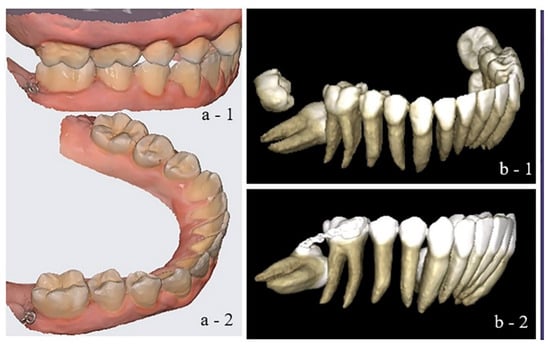

Figure 3. Digital Planning of the Printed Dento-alveolar Anchorage System (PDaA): Integration of intraoral scans and CBCT data for both upper and lower dental arches in occlusion. The visualization includes: the position of the impacted tooth relative to the first molar (red); the positions of the roots within the mandibular arch (green); the design of the appliance’s anchorage component relative to the impacted mandibular second molar (blue); and buccal and occlusal views of the design.

Therefore, the workflow relies on high-accuracy digital records—CBCT, intraoral scans, and photographs, acquired with calibrated devices and registered through a validated protocol, enabling precise transfer from virtual design to device fabrication and clinical delivery. The digital workflow began with the integration of intraoral scan data (STL files) and segmented CBCT images (DICOM files), enabling comprehensive 3D treatment planning Figure 3. Accordingly, the CBCT-derived root anatomy of the anchorage teeth and the true position of the impacted MM2 are registered onto the working digital models. Using CAD/CAM software (Exocad 3.0 Galway), the anchorage zone was defined, and a metallic extension was designed to project into the retromolar space. The extended arm (cantilever) emerges from the base of the lingual framework and may be positioned lingually or buccally, or configured to circumferentially encircle the molar site. The position of the extension was adapted to the occlusal plane to avoid interference with interarch relationships and aligned with the alveolar ridge anatomy to prevent irritation of adjacent soft tissues.

The digital planning includes precise assessment of the metallic extension’s position relative to the impacted mandibular second molar, evaluation of occlusal contacts, and analysis of the transverse and sagittal dimensions of the retromolar space. Depending on the position of the impacted molar, one or more hooks for elastic elements were incorporated into the extension, allowing for precise direction of the traction forces and potential vector modification during the course of treatment Figure 4. The anchorage design could be positioned lingually, buccally, or extended across the entire retromolar area. Once a segment of the extension fulfilled its function, it could be removed by cutting with a carbide bur to reduce the weight and bulk of the appliance.

Design was performed using Exocad 3.0 Galway software, and the final design was exported in a format compatible with 3D metal printing. The anchorage system was fabricated using Wirobond C+ metal powder (BEGO Medical GmbH, Bremen, Germany), composed of 63.3% Cobalt (Co), 24.8% Chromium (Cr), 5.3% Tungsten (W), 5.1% Molybdenum (Mo), and 1.0% Silicon (Si). An offset of 0.08 mm was applied to the rings and contact zones [32]. The manufacturing process employed laser sintering (SLM/SLS) technology using the TruPrint 1000 system (Trumpf Group, Ditzingen, Germany). During fabrication, the powder was melted layer by layer using a high-energy CO2 laser until the final structure was completed Figure 4. After printing, support structures were removed. Based on the team’s six years of experience working with this manufacturing system, we rely on the predictability and accuracy of appliance printing, which prevents the generation of residual stresses. The alloy used contains no nickel, thereby reducing the risk of allergic reactions in patients during orthodontic treatment. Numerous studies have already confirmed the mechanical properties, electrochemical behavior, and biocompatibility of the selected alloy [33,34].

The design of the PDaA can incorporate additional elements to support the subsequent phase of orthodontic treatment (i.e., the fixed appliance stage). The integration of printed buccal tubes onto the bands of the lower first molars (as illustrated in one of the PDaA designs in Figure 4, or printed brackets on bands encompassing the premolars, eliminates the need to remove the anchorage system when transitioning to the next treatment stage. Such integrated elements are particularly advantageous in segmental treatments primarily focused on the traction of MM2.